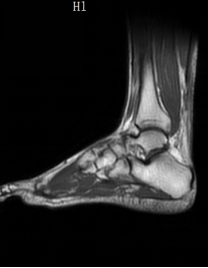

术前核磁

患者杨先生(化姓)是一名体育运动爱好者,前几日参加篮球比赛时,因发力不当,左脚落地时,踝部瞬间剧痛,无法站立。当即被朋友送到了当地医院就诊,磁共振检查显示:左跟腱断裂。随后,杨先生迅速转至我院骨外二科接受进一步住院治疗。